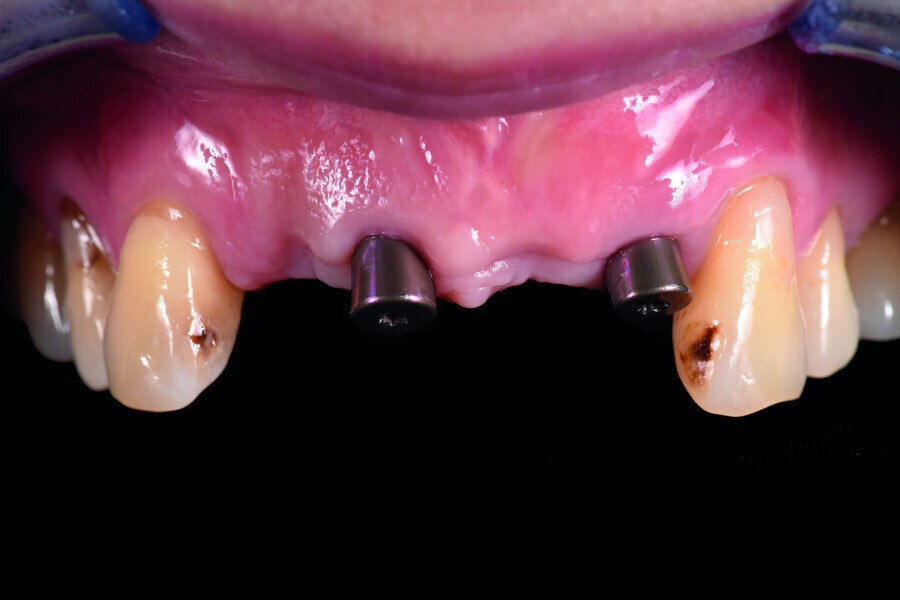

Fig. 12: Two impression copings connected for the implant level impression.